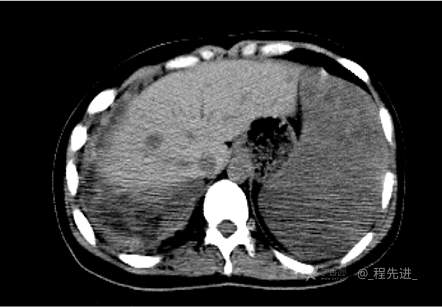

患者性别:女

患者年龄:26岁

简要病史:反复胸闷、气喘、咳嗽半年